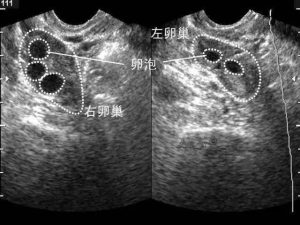

卵泡是在卵巢皮质内由一个卵母细胞和其周围许多小型卵泡细胞所组成。根据卵泡发育过程的形态和功能变化,可分为原始卵泡、生长卵泡和成熟卵泡三个阶段。“卵巢”最主要的功能是产生“卵子”,卵子在卵泡里和卵泡同步成熟,发育良好的卵子是试管婴儿成功的保证。但是卵子太小,肉眼看不见,在试管婴儿中,为了成功取到优质的卵子配成胚胎,只能间接地通过观察卵泡来推测卵子的发育情况。卵泡发育最简单、最直观的评估是通过超声观察,每个周期通过3-4次的超声监测,可以观察到有没有正常的卵泡生长、发育、以及何时可进行取卵手术。

在试管婴儿超促排卵过程中,卵泡监测是为了评价卵巢刺激的效果与决定取卵的时间。当两个以上卵泡直径大于18mm,便可当日“打夜针”注射人绒毛促性腺激素(HCG),促使卵泡成熟。在注射HCG后36小时取卵。成熟卵泡圆而饱满,内壁薄而清晰,有张力。卵泡数量过多,要警惕卵巢过度刺激综合征的发生。每个人对促排卵药的反应也不一样,有的人卵泡前期长得慢,也不用过于担心,医生也会根据个人情况不同调整药物的。